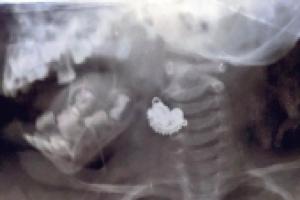

दो साल की बच्ची ने निगला झुमका, डॉक्टरों ने किया सफल ऑपरेशन

हल्द्वानी, अमृत विचारः सुशीला तिवारी हॉस्पिटल में दो साल की एक बच्ची पहुंची। उसने गलती से झुमका निगल लिया। हॉस्पिटल में उसका सफलतापूर्वक ऑपरेशन किया गया। गर्मियों में छोटे बच्चे अक्सर ठंडक पाने के लिए सिक्के, बटन बैटरी, झुमके, खिलौनों...